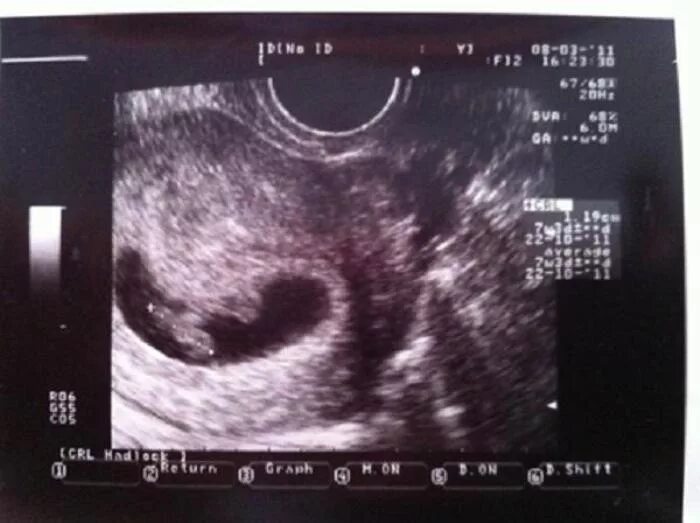

7 недель беременности симптомы